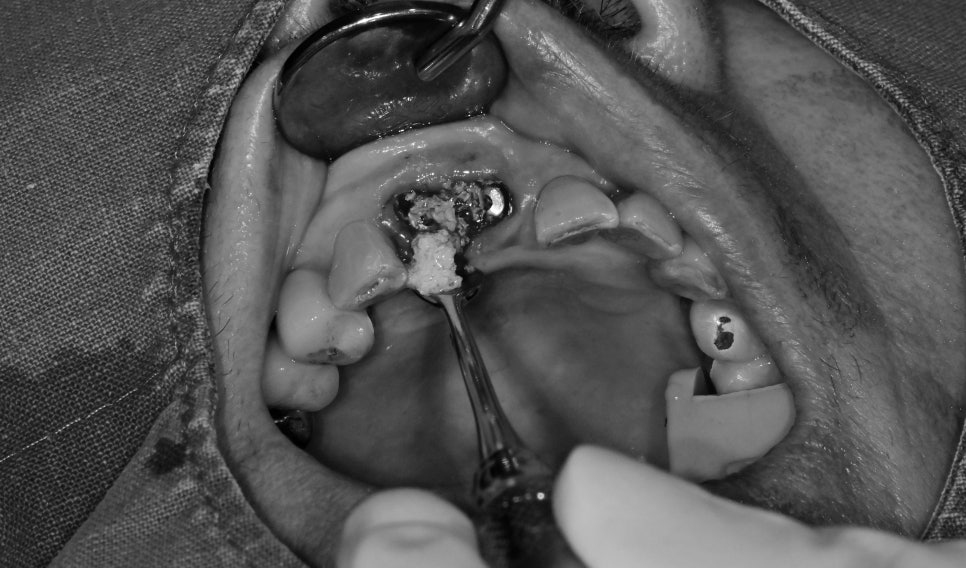

발치와 동시에 임플란트 수술을 먼저 진행했습니다

치주염에 의해 부족한 뼈는 치조골 이식이라는 뼈이식을 통해

부족한 볼륨을 회복시켜줬습니다.

앞니 수술 시 임플란트의 초기 고정이 좋으면 보통 당일 치아까지 완성을 합니다

하지만

환자분께서는 주변 잇몸이 좋지 않았고, 고정력도 약했기 때문에

심미적으로 불편하시겠지만 임시틀니를 뺐다 겼다 하시는 치료방법을 선택했습니다